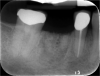

The patient wanted an implant-supported crown to restore the right mandibular first molar, which had been extracted after recurrent caries, endodontic treatment, and development of a periapical lesion. The site was grafted with bone grafting material and a biological membrane and allowed to heal for 6 months. A periapical radiograph was then taken (Figure 6), which showed the socket areas to be well condensed, with mature-looking bone. A CBCT scan was taken to facilitate implant-placement planning.

Fig 6. Periapical radiograph, single missing tooth.

Figure 6